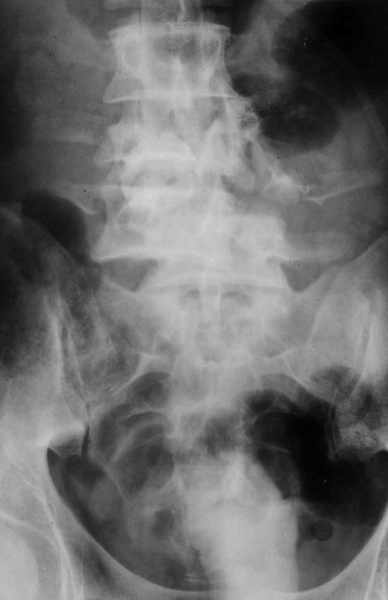

Высылаю рентгенограммы. Спасибо за рекомендации. Наша тактика согласуется с вашими рекомендациями за исключением транспедикулярной фиксации - у данного пациента на наш взгляд предпочтительнее наружная транспедикулярная фиксация (Курганский аппарат). Погружная конструкция предпологает одномоментную репозицию до выполнения забрюшинного доступа и ревизии переломов что теоретически может привести к повреждению дурального мешка и корешков. АВФ позволит восстановить ось позвоночника и смещение по длине непосредственно под контролем глаза на этапе внебрюшинного доступа. Сколько сегментов замыкать? Я думаю может потребоваться замкнуть и сегмент L2-L3. Предполагается использовать тело L4 для костной пластики таким образом, чтобы ширина спиномозгового канала на уровне оперированных сегментов была увеличена. Фиксация тел позвонков вентральной пластиной.